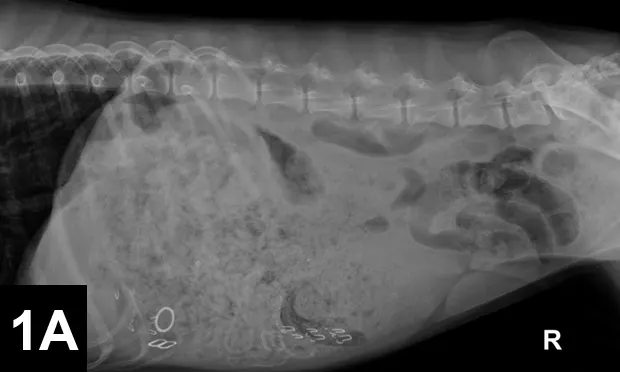

Abdominal Radiography: Right lateral (Figure 1A, above) and VD views (Figure 1B) of the abdomen were obtained.

Radiographic Findings: The right lateral view (Figure 2) showed severe gastric distension (white double headed arrow) with granular ingesta, intermediate opacity oval structures seen in the ventral stomach on the lateral view (suggesting rubber bands or hair elastics), and various metallic structures (compatible with bra straps and hooks). The small and large intestines are displaced caudally by the gastric distension. The gas-distended small intestine (white bar) measured up to 24 mm and the height of the L5 vertebral body (black bar) was 11 mm; this gives a small intestinal to L5 ratio of 2.2, which is much greater than the upper limit of 1.6 for normal small intestine to L5 height ratio.1

Comments: It is tempting to see the most obvious radiographic abnormality (ie, the large amount of foreign material) but miss the more subtle abnormality, such as the small intestinal distension in this case. Measuring the distended small intestine and dividing it by the height of the L5 vertebral body (not including the canal and spinous process) can be used as a measure of normal or an abnormally distended (>1.6) small intestinal diameter.